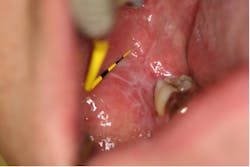

Frictional keratosis

Frictional keratosis (figure 1) is a white keratotic lesion on the oral mucosa that results from a chronic mechanical friction by various oral irritants or habits. These lesions appear on the keratinized or nonkeratinized tissues and present as diffuse plaques, pale translucent to dense white and irregular.2 As the name implies, frictional keratosis is diminished with removal of the causative factor. If cessation of the irritant does not result in clinical improvement, a biopsy should be performed.